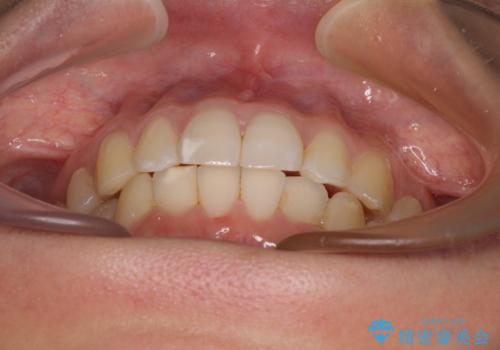

- 上下のクロスバイトと前歯のデコボコを気にして来院された患者様です。

インビザラインを用い、IPR(歯と歯の間を削る)と歯列全体を拡大させることで、歯並びを整えていくこととしました。

下の歯が隠れてしまうほどでしたが、深い咬み合わせも改善され、顎への負担も軽減されました。